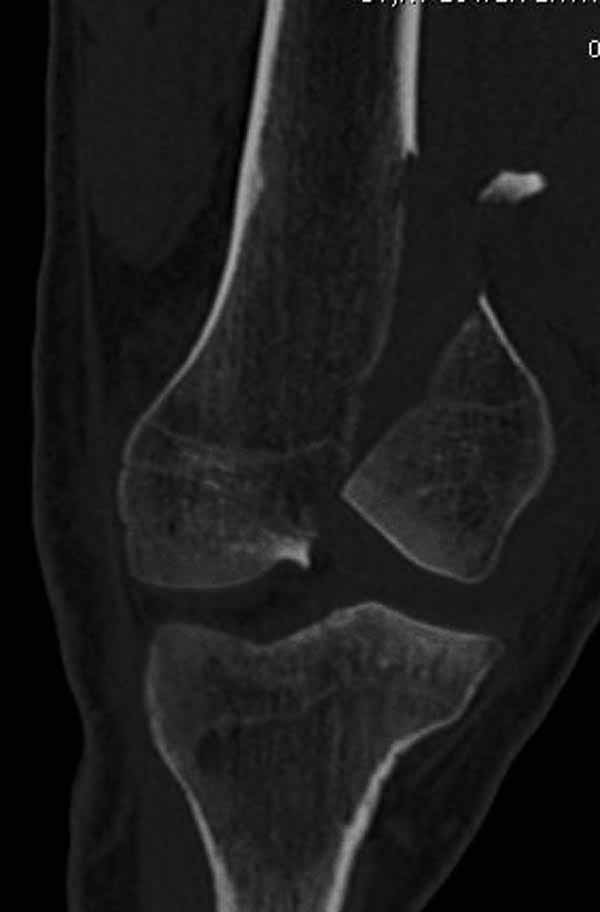

И не обратите, коллега, пока не сделаете четкие анфасные снимки (лучше с дистракцией) где будет четко визуализироваться малоберцовая кость. Думается, что и КТ здесь будет уместно, дабы не пропустить возможное флексионное повреждение (перелом Hoffa).

А теперь по поводу лечения перелома. Среди всех чрез/меж-мыщелковых переломов в 38% сопровождются переломом в корональной плоскости, т.е перелом Hoffa. Nork et al, J Orthop Trauma, 87:564, 2005.

У больных как в этом случае, с вовлечением двух мыщелков правильно, что сделали вытяжение до операции. Здесь имеется флексионный компонент на другой стороне, и я бы рекомендовал операцию делать из двух доступов. Сперва фиксировать медиальную колонну custom made пластиной, обычно 1/3 тубулярной пластиной в 4.5 мм, потому что пока производители опаздывают с медиальной пластиной.

Однако в случае, представленном Константином Никитиным, не может быть применён ни ретроградный ни антеградный остеосинтез. Причина - нереально выполнить вышеуказанные необходимые требования, касающиеся дистальных блокирующих винтов. Из-за низкого перелома латерального мыщелка (перелом Hoffa) невозможно через него провести хотя бы 2 блокирующих винта, поскольку линия перелома мыщелка расположена либо на уровне верхушки межмыщелковой ямки либо незначительно проксимальнее. Поэтому авторам, с моей точки зрения, необходимо прислушаться к рекомендациям Джолдаса.